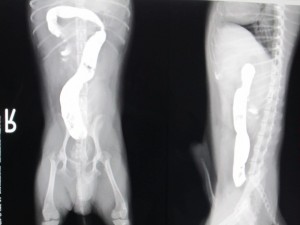

術中

術中の様子です。

異常を起こしている腸がよくわかります。

腸切開して異物を摘出しました。